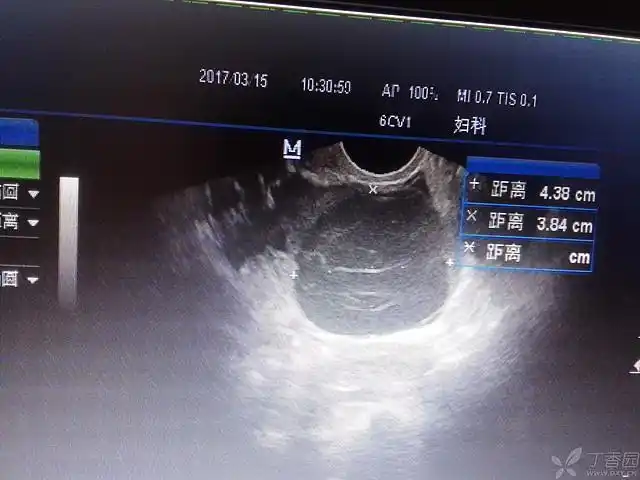

卵巢子宫内膜异位囊肿(巧克力囊肿)

看看这个巧克力囊肿吧,有点大 - 超声医学讨论版 - 爱爱医医学论坛

巧克力囊肿8厘米多

左附件区囊性包块,大家帮看看是巧克力囊肿吗?